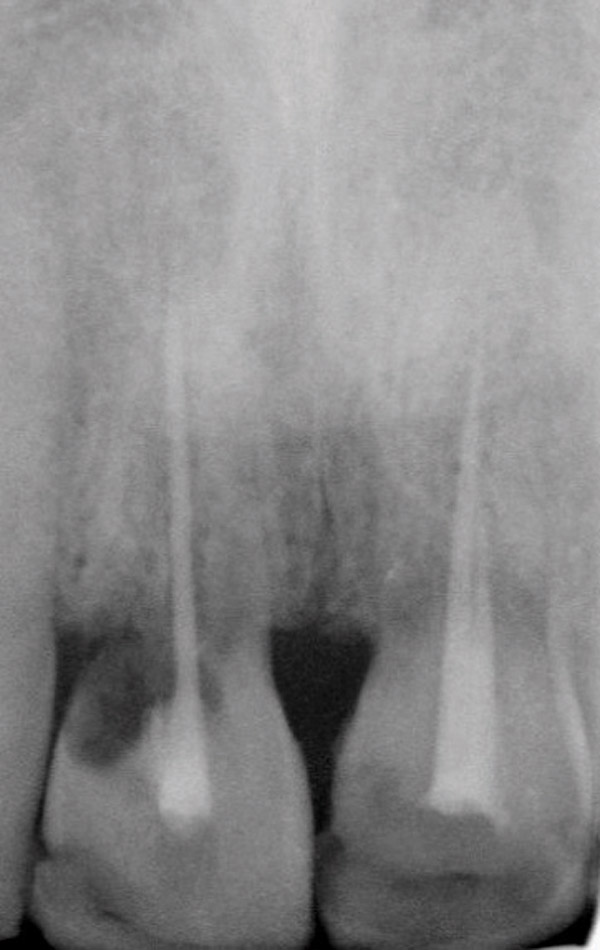

Figure 14  Initial periapical radiograph revealed internal root resorption of teeth Nos. 8 and 9 with almost complete horizontal severing of the crowns from the roots.

Figure 14